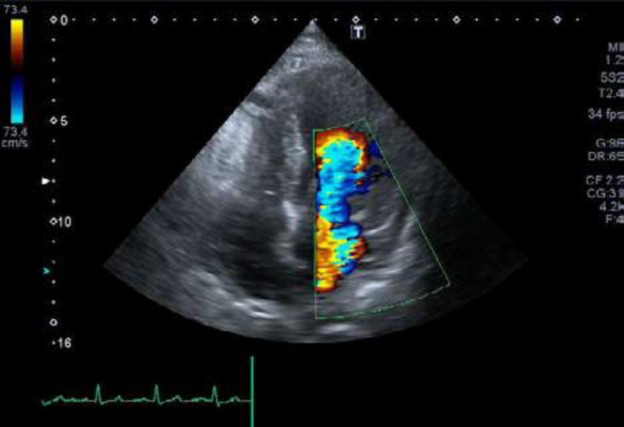

Chordal Rupture (2/2) • Video • MEDtube.net

medtube.net

medtube.net

rupture chordal echocardiogram video

Double Valve Replacement For Acute Spontaneous Left Chordal Rupture

cardiothoracicsurgery.biomedcentral.com

cardiothoracicsurgery.biomedcentral.com

ruptured chordae mitral echocardiogram rupture transesophageal anterior chordal aortic leaflet incompetence chronic spontaneous acute